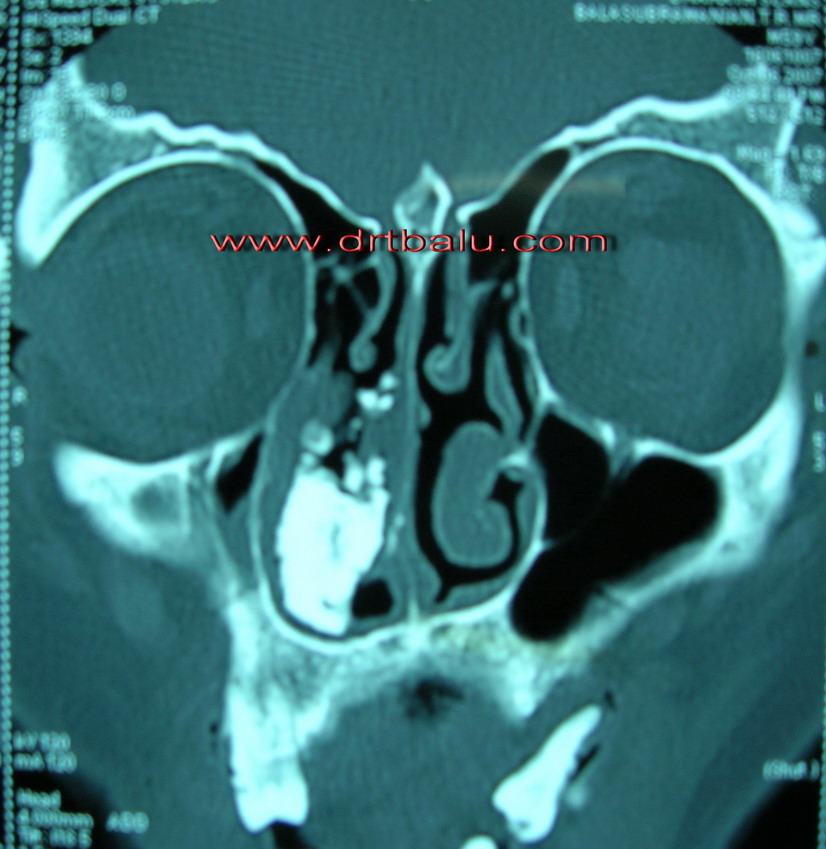

CT coronal view of nose and sinuses showing Rhinolith

These patients have unilateral nasal discharge, which may be serosanguinous in nature. As the rhinolith increases in size, the symptoms of nasal obstruction become more pronounced and the patient may manifest with unilateral purulent nasal discharge. Swelling of the nose, face epiphora could be some of the symptoms.

On probing the presence of a stony hard structure could be identified. It is common in the inferior meatus